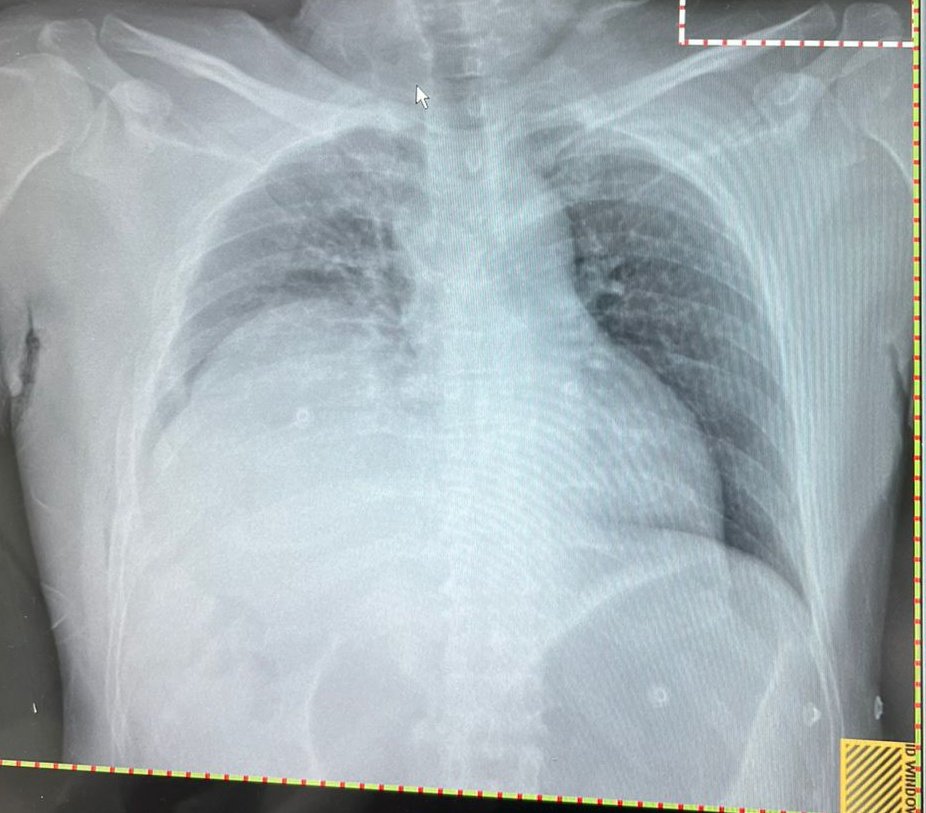

#TraumaTips

50 M

RTC

Primary unremarkable

Except for RR of 30

Secondary: Rt multiple # ribs

Portable CXR done in Peripheral hospital ⚡👇

Retrieved -->

I took him for Laparatomy

Why?